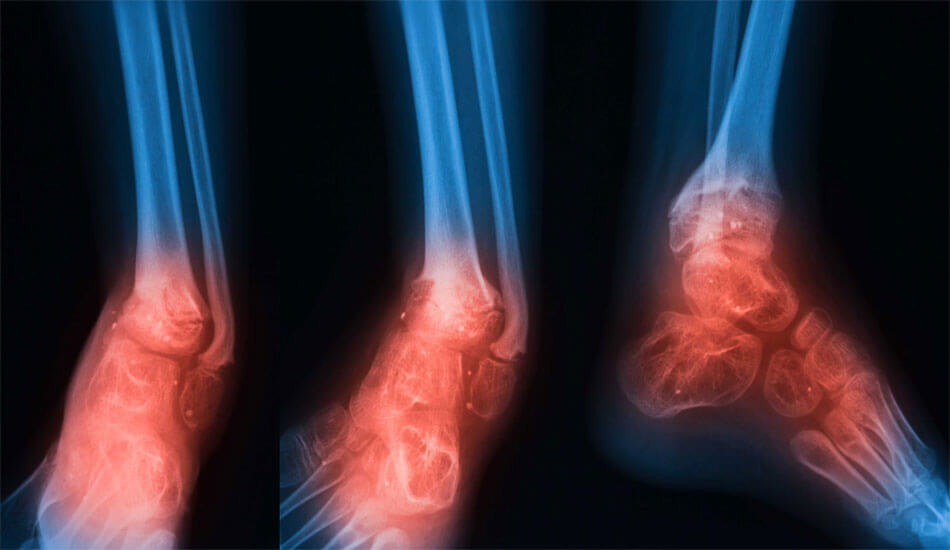

Οι ορθοπεδικές λοιμώξεις μπορεί να εκδηλωθούν με διάφορους τρόπους, ανάλογα με τη θέση και τη σοβαρότητα της λοίμωξης. Μερικά κοινά συμπτώματα περιλαμβάνουν πόνο, οίδημα, ερυθρότητα, ζεστασιά και ευαισθησία γύρω από την πληγείσα περιοχή. Σε πιο σοβαρές περιπτώσεις, η μόλυνση μπορεί να προκαλέσει πυρετό, ρίγη και άλλα συστηματικά συμπτώματα.